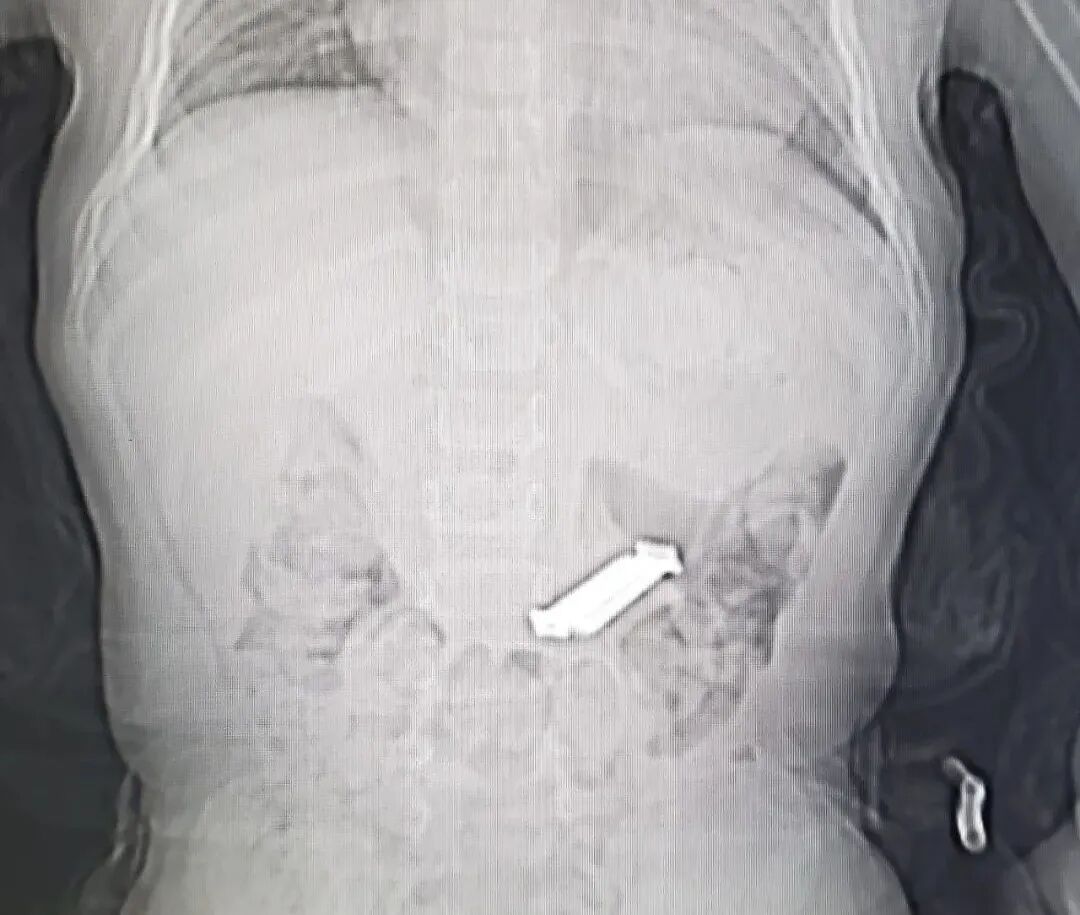

但是如何将5枚4公分长的铁钉通过近乎直角的十二指肠球降交界转角处,以及再从狭小的幽门口取出,成了又一大难题,面对不断出现的困难,颜主任凭借多年的内镜经验,及时调整圈套器夹取铁钉的距离和方向,改变铁钉与腔道的角度,顺利将5枚铁钉拉到胃内,并将其全部取出体外,为确保患儿体内已无铁钉,急诊行床旁腹部摄片检查,结果提示患儿腹部未查见高密度金属影,宣告所有铁钉已全部取出,顿时整个手术室一片欢呼。